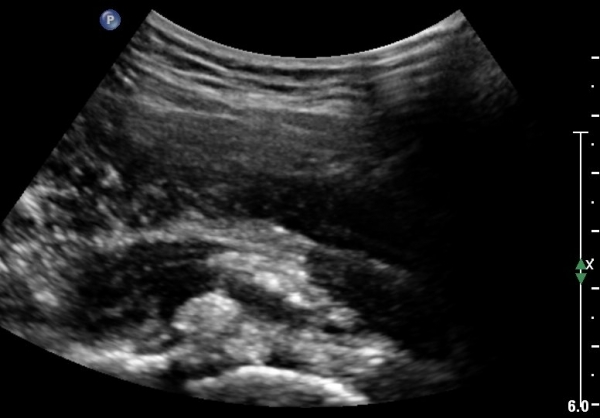

ÃÊÀ½ÆÄ°Ë»ç: °í°üÀý ¾ÕÂÊ Á¾´Ü¸é °Ë»ç¿¡¼­ °üÀý³¶ÀÌ µÎ²¨¿öÁö°í °æ¹ÌÇÑ °üÀý³» ºÎÁ¾À» º¸ÀÓ(»çÁø1, 2)

°í°üÀý ¿ÜÃø, ¹Ù·Î µÚ Á¾´Ü¸é°Ë»ç¿Í Ⱦ´Ü¸é °Ë»ç»ó °üÀý ¿Í¼øºÎÀ§¿¡ Ä¿´Ù¶õ °í¿¡ÄÚ ¼®È¸È­°¡ °üÂûµÊ(»çÁø 8, 9)